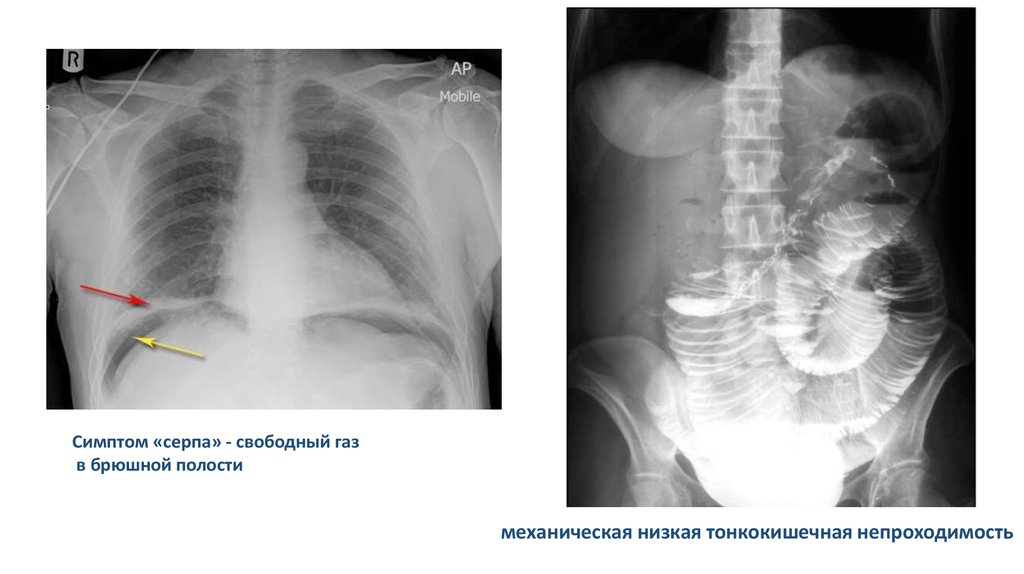

Симптом «серпа» - свободный газ

в брюшной полости

механическая низкая тонкокишечная непроходимость

Признаки кишечной непроходимости

Чаши Клойбера

Кишечные арки